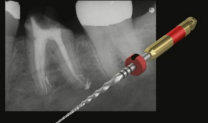

Endodontie

Zähne mit Entzündungen des Zahnnerves (Pulpa) können langfristig durch fachgerechte Wurzelbehandlungen erhalten werden. Wir wenden moderne anerkannte Verfahren an.